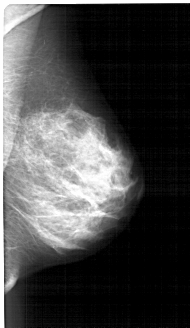

A_1391_1.RIGHT_MLO

LEFT_MLO LINES 5236 PIXELS_PER_LINE 3076 BITS_PER_PIXEL 12 RESOLUTION 43.5 OVERLAY